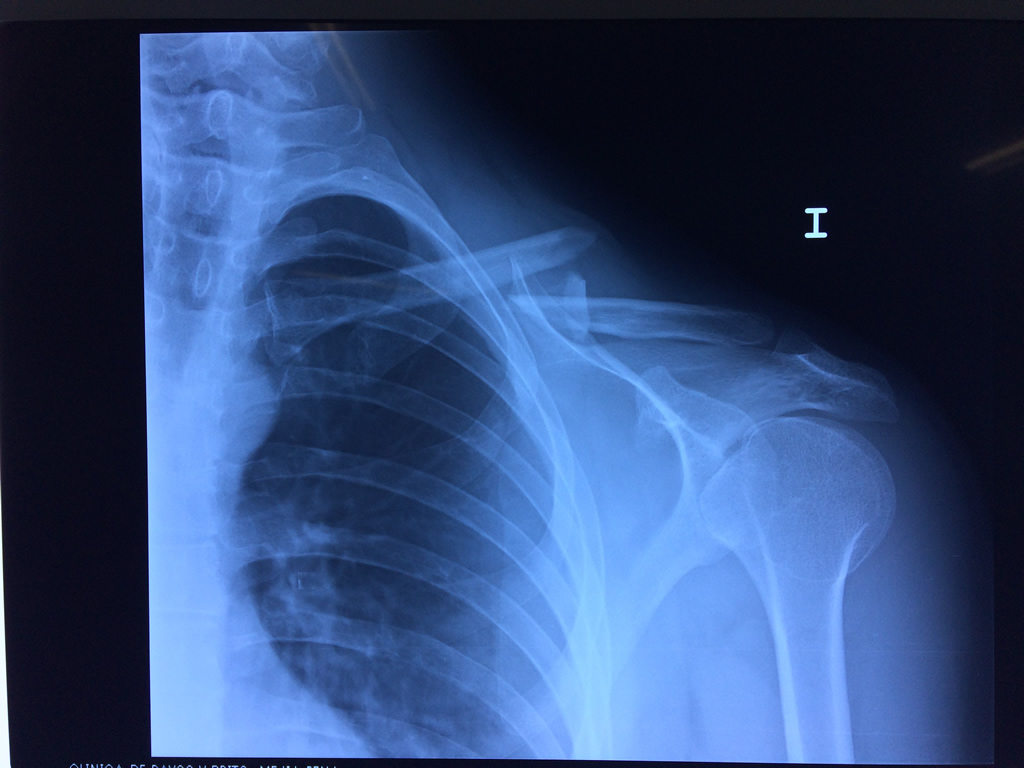

Cirugías de Húmero - Clavícula